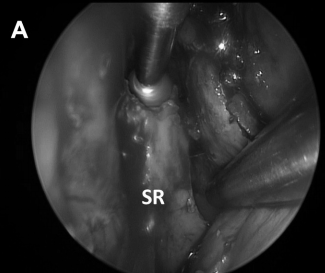

▼进行了对侧单侧入路和宽蝶窦切开术(图8A)。

CD,斜坡凹陷;S,蝶鞍;SR,蝶嘴;T,肿瘤。